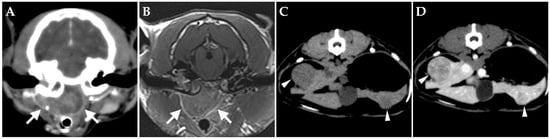

At the time of initial examination, she weighed 3.60 kg (body condition score 3/5) with no obvious abnormalities in posture or gait. Minimal cerumen was present, and cervical lymph nodes were not enlarged. Cranial neurologic examination revealed disturbance of the right facial nerve and abnormalities of the hypoglossal nerve (narrowing of the right eyelid fissure, loss of right menace reaction, loss of right eyelid reflex, decreased right corneal reflex, decreased right maxillary and mandible perception, and folded tongue). No history of seizures was elicited. Complete blood count, blood biochemistry, and coagulation test were within the reference ranges, and urinalysis showed no obvious abnormalities. Negative results were obtained for feline immunodeficiency virus antibody and FeLV antigen test (SNAP FIV/FeLV Combo Test; IDEXX Laboratories, Westbrook, ME, USA). Computed tomography (CT) of the head without anesthesia or contrast media was performed to confirm the status of the middle ear, revealing space-occupying lesions in bilateral tympanic bullae (Figure 1). No bony changes or other obvious abnormalities were identified outside the middle ear, including in the nasal cavity. The lesions within the tympanic bullae resembled effusion or soft tissue, so infection and neoplastic disease were the differential diagnoses.

Figure 1. Transverse computed tomography (without anesthesia or contrast media) of the head at the level of the middle ear of the cat at first presentation in the soft tissue window (A) and bony window (B). The ventromedial compartment of the left tympanic bulla and the ventromedial and dorsolateral compartments of the right tympanic bulla are occupied by fluid/soft tissue attenuating materials. No bony abnormalities are evident.